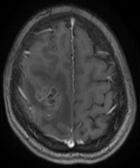

Une localisation trompeuse

Dr Fatima Zohra Guettaf Centre Anti Cancer ; Faculté de Médecine Université Blida 1 - Blida et Dr Yamina Yousfi (Pathologiste - Faculté de Médecine Université Blida 1 ; CHU Douera - Alger)

Patiente âgée de 27 ans, mère d’un enfant sans ATCD neurologiques particuliers, hospitalisée en neurochirurgie le 20/11/2016 pour un syndrome d’HIC, épilepsie pariétale, un flou visuel, vertiges, paresthésies et faiblesse musculaire.

Examen neurologique :

- hémiparésie brachio-crurale gauche

- IK 90%

Quels examens demanderiez-vous ?